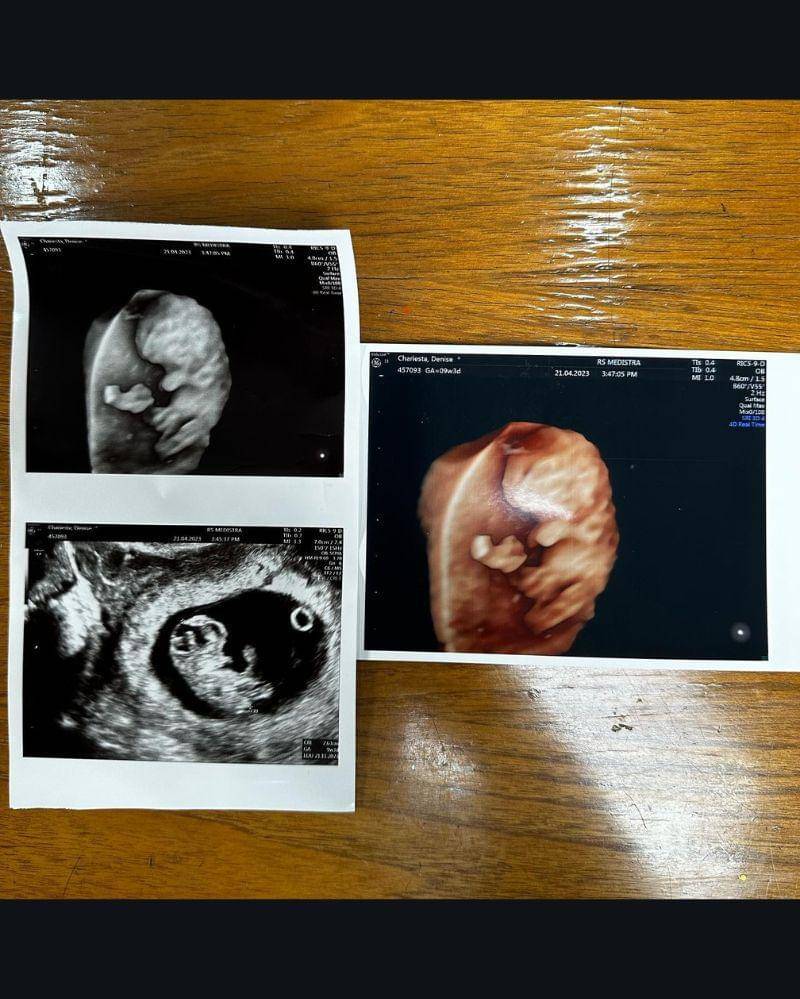

Pada Senin (24/4/2023), ia memamerkan hasil USG terbarunya. Publik yang tadinya sempat geger dan menghujat kehamilan Denise kini sudah banyak yang bersimpati di kolom komentarnya.

2. Janin dalam kandungannya aktif, Denise mengaku senang

Melihat jabang bayi dalam kandungan menjadi momen yang dinantikan Denise. Setiap melakukan USG ia selalu senang mengetahui keadaan jabang bayinya yang sehat dan aktif.

Terakhir kali USG Denise begitu bahagia karena menurut dokter bayinya tidak bisa diam. Di dalam kandungan "Baby Beruang", panggilan sayangnya untuk si Janin terus bergerak.

"Yeay kata dokter baby-nya sehat nggak bisa diem kayak mamanya soalnya gerak-gerak terus," tutur Denise.

6. Tunjukkan foto USG, Denise sebut: tidak ada bayi terlahir haram

"Kehamilan ini mengubah hidupku. Utunku yang lucu adalah segalanya. Happy 10 week Utun," tuturnya.